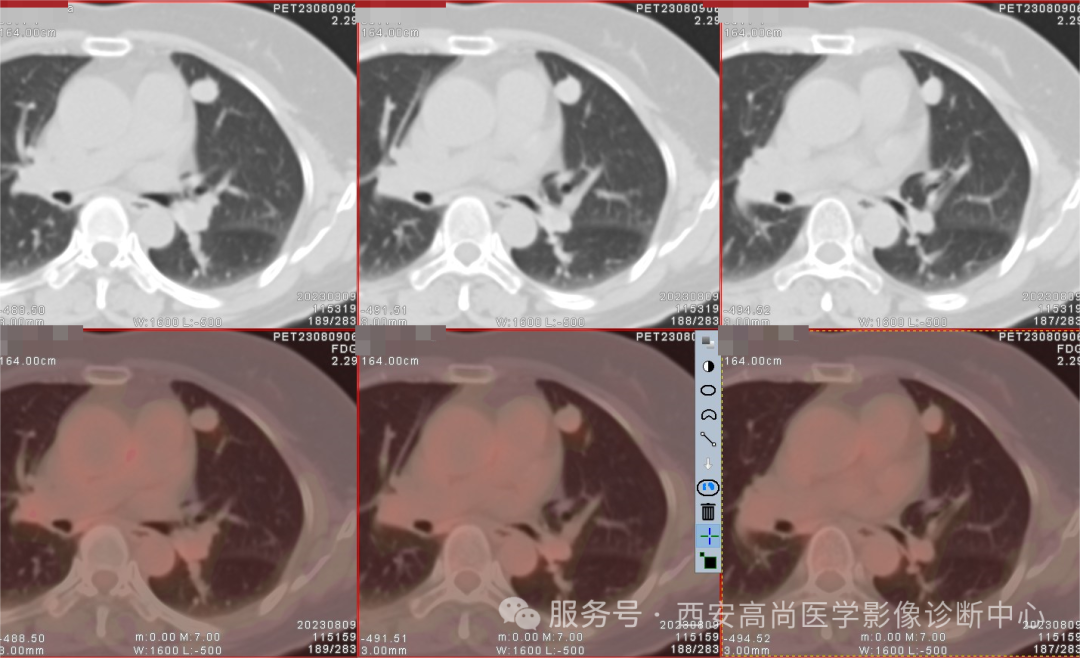

检查所见:右肺中叶见不均匀团块状软组织病变,大小约 8.0 cm×6.3 cm×7.0 cm,右肺中叶支气管完全闭塞,肿块呈高低混杂密度,边界较为光整,其内见点状钙化灶,呈不均匀放射性摄取异常增高,SUV 最大值介于 2.6-6.0。

影像学诊断:右肺中叶不均匀团块状软组织病变,肿块呈高低混杂密度,呈不均匀 FDG 代谢增高,结合病理,考虑为肺低度恶性肿瘤可能(孤立性纤维瘤?)建议穿刺病理检查明确。

研究表明18 F-FDG PET 上 PSP 可表现异常放射性浓聚,一般为轻到中度 ,影响 PSP 18 F-FDG 摄取因素尚不清楚,有学者研究认为 浓聚的高低可能与肿瘤大小相关。瘤体小于 2.5,FDG 呈轻度摄取增高。瘤体大于 4 cm,SUV 最大值>2.5。

三、 通过 18-FDG PET/CT SUVmax 来鉴别孤立性纤维瘤良恶性具有较大价值。孤立性纤维瘤国内外 PET/CT 显像资料很少,研究 PET 特征发现:恶性代谢率 SUVmax(中位数:3.6 范围:2.5-4.9),比良性代谢率(中位数:2.0,范围:1.2-3.1)略高,差异有统计学意义。